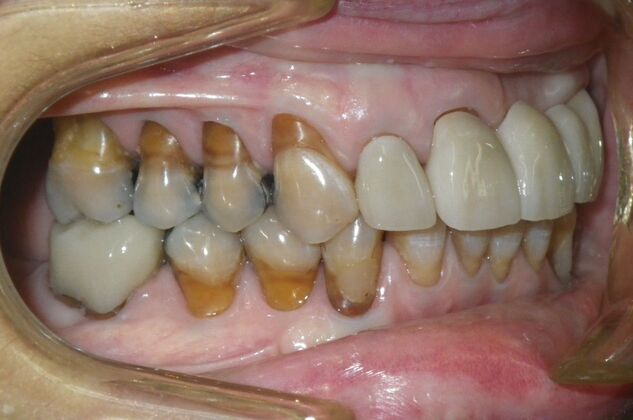

Cosmetic Changes with Veneers and Crown and Bridge: Case 6

Description

This patient had long term acidic erosion of upper and lower teeth eventually leading to loss of upper left central and lateral incisors. While she was somewhat happy with replacement of her front teeth with a removable appliance, she really desired to have something she didn't have to remove. So patient opted to be conservative with two single unit crowns as well as a four unit anterior bridge. These were fabricated using all ceramic without metal